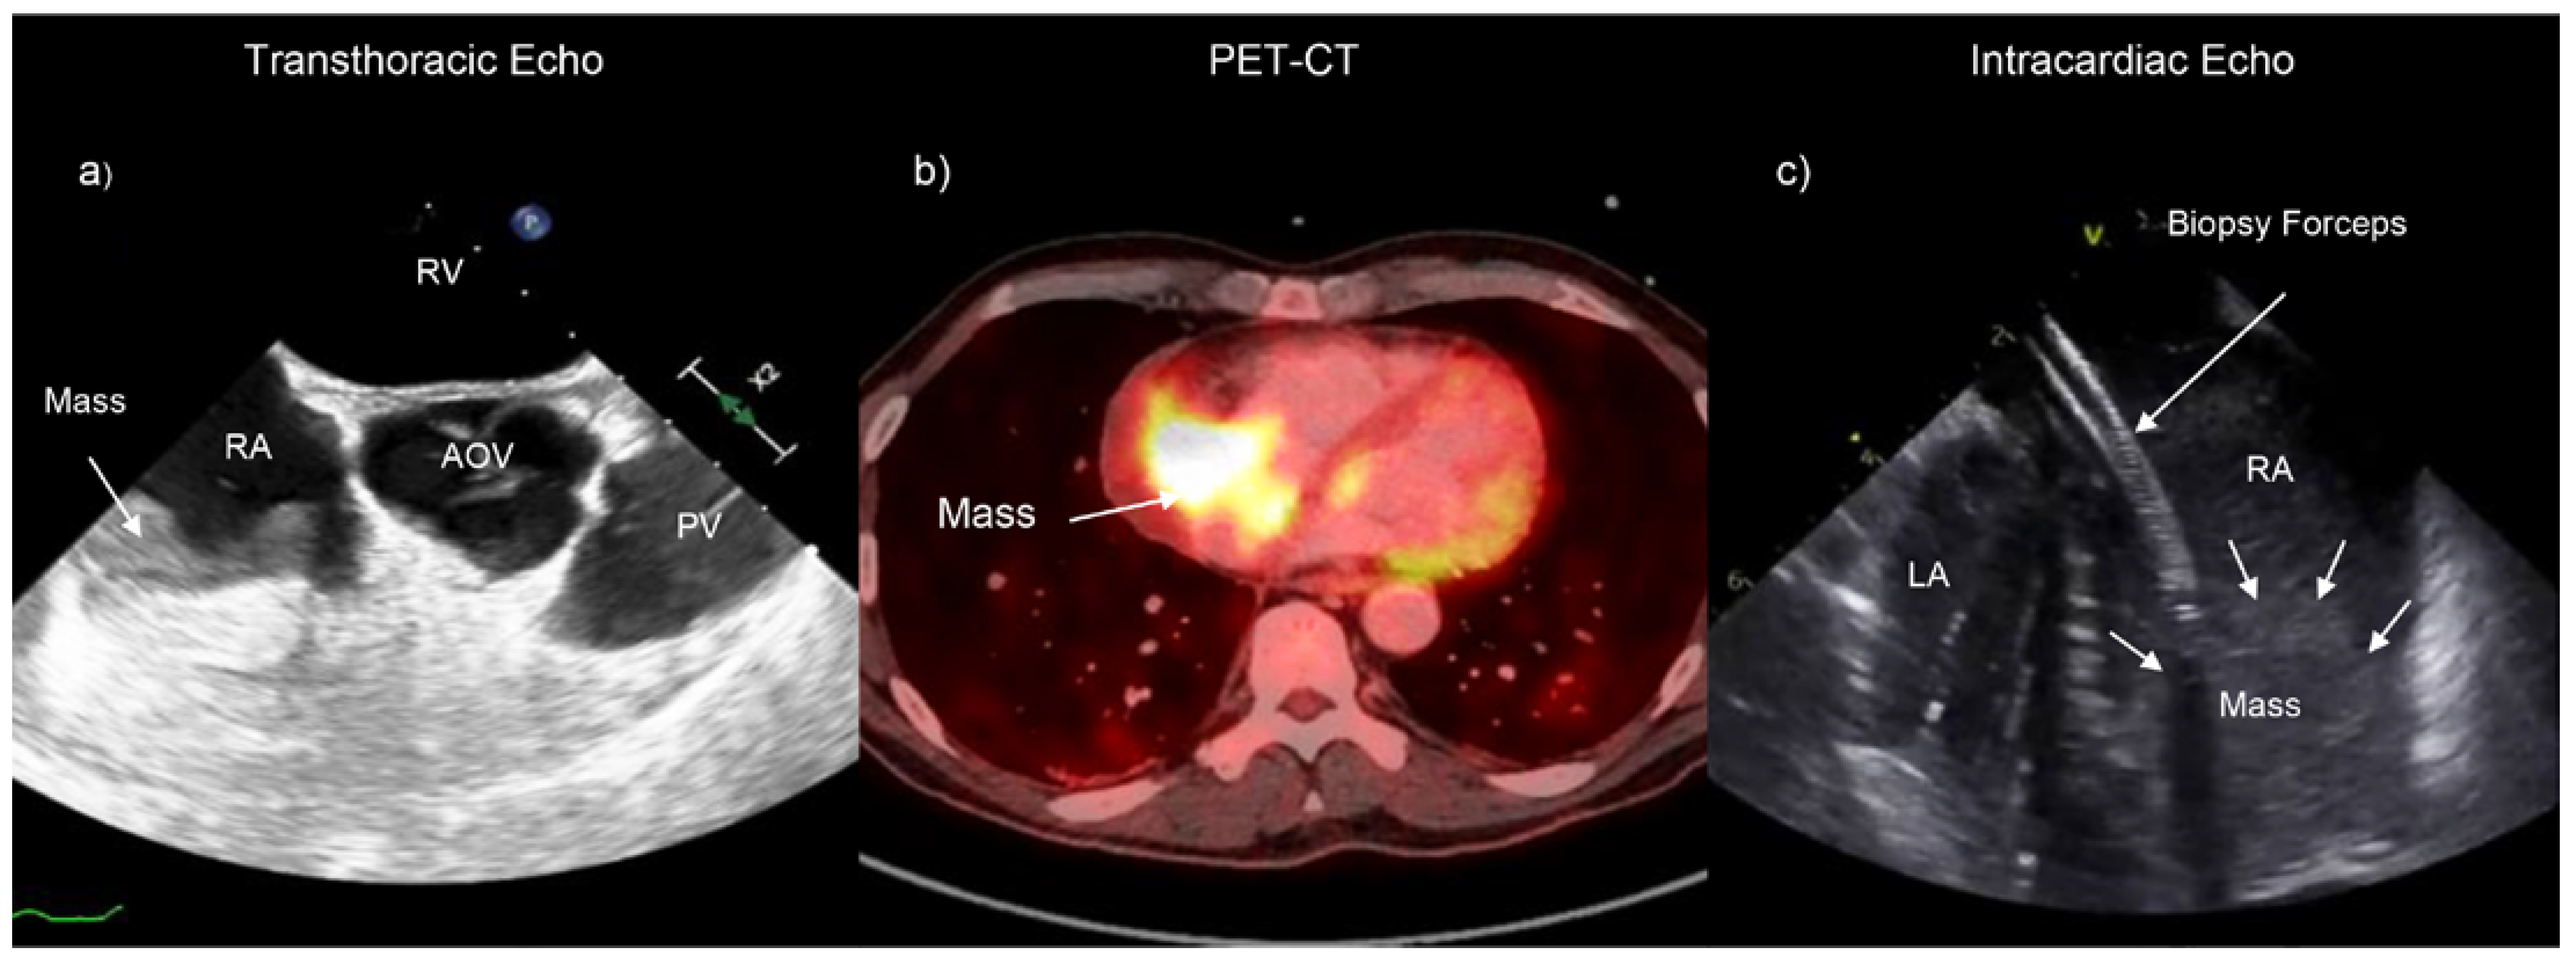

Intracardiac Echocardiography to Guide Biopsy of an Intracardiac Right-Sided Mass

Case Report